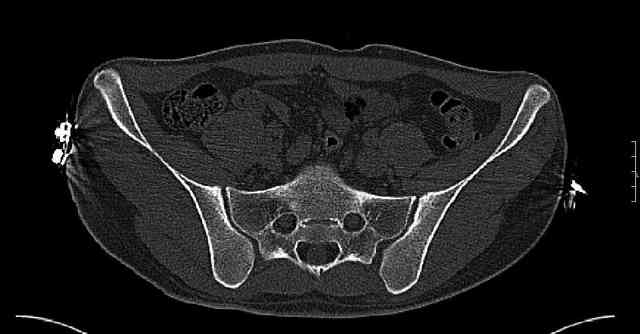

The last two images from the 3-D CT scan certainly makes the fracture look worse than the plan radiographs.

Some more images. Does it help to guess which part of the acetabulum is displaced?

Normal appearing SI joints and a healed posterior column limb... my bet's on caudal segment displacement.